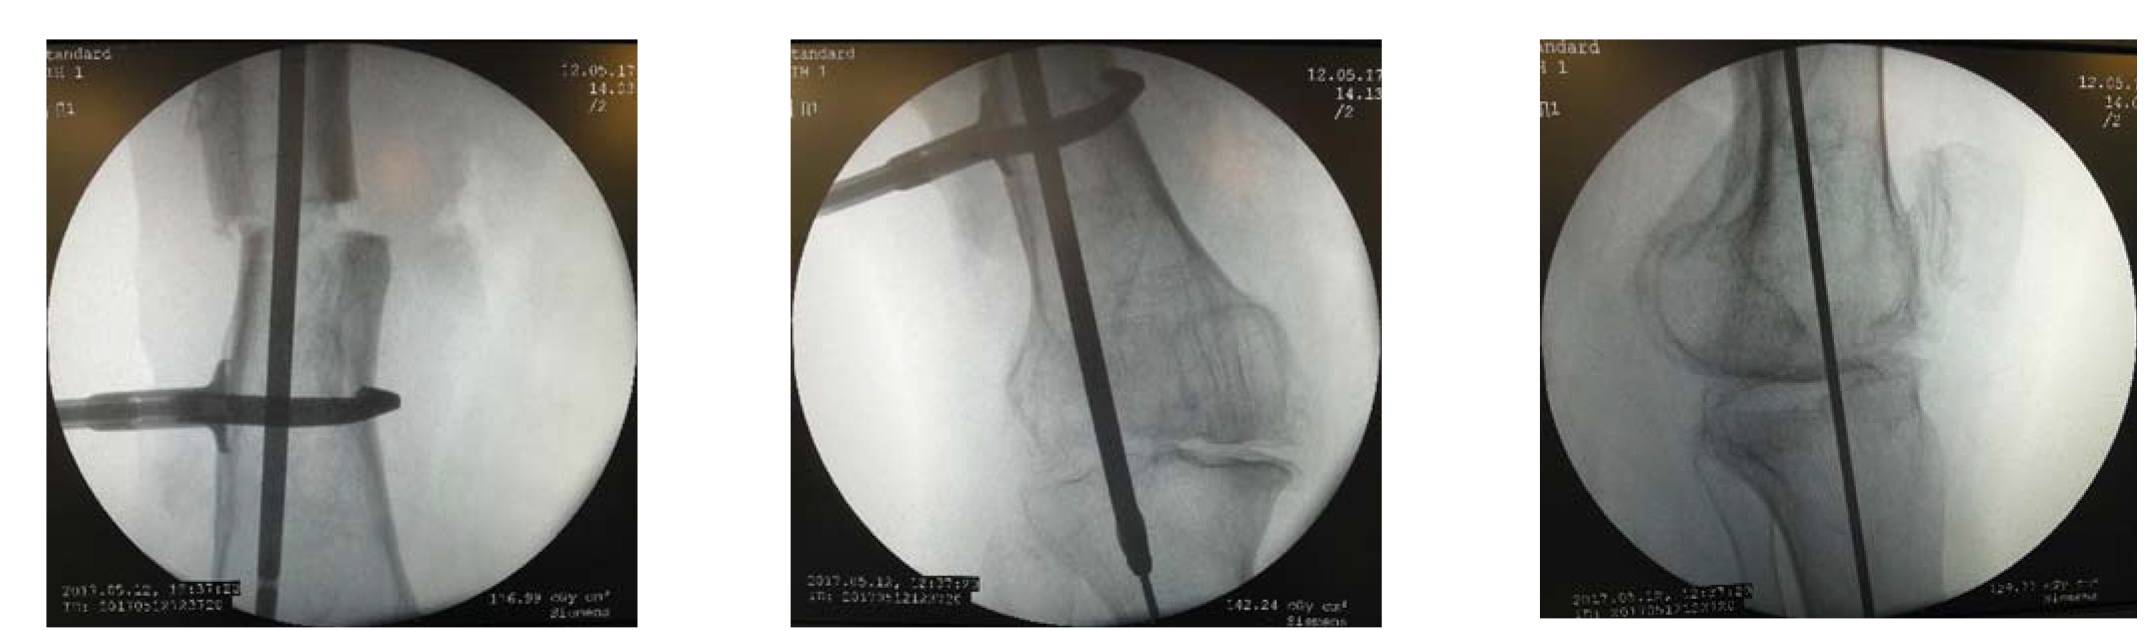

Пациентке 12.05.17 было выполнено оперативное вмешательство. Первым этапом осуществили артроскопию правого коленного сустава: с помощью вапоризатора и шейвера были удалены рубцовые ткани, пересечены соединительнотканные перемычки между суставными поверхностями бедренной и большеберцовой кости. Мягкотканным и костным шейверами удалены остатки хрящевого покрова и субхондральной кости на глубину 1–3 мм с нагружаемых суставных поверхностей бедренной и большеберцовой костей (рис. 2).

Для возможности манипулировать дистальным фрагментом после остеотомии вторым этапом из разреза кожи длиной 3 см на уровне нижней трети бедренной кости (под вершиной деформации) был установлен экстракортикальный фиксатор (ЭФ) [13] (рис. 3). ЭФ обеспечивает стабильную фиксацию костного фрагмента, при этом костномозговой канал остается свободным.

Затем была произведена кортикотомия с остеоклазией бедренной кости на высоте ее деформации. Используя ЭФ в качестве манипулятора (джойстика), устранили имевшуюся многоплоскостную деформацию бедренной кости. Проводник был трансартикулярно введен в костномозговую полость для ее рассверливания (рис. 4).

Рис. 2. Артроскопическая картина этапа удаления нагружаемых суставных поверхностей бедренной и большеберцовой костей.

Fig. 2. Arthroscopic picture of the stage of removal of the loaded articular surfaces of the femur and tibia.

Рис. 3. Экстракортикальный фиксатор: внешний вид (а); установление экстракортикального фиксатора (б).

Fig. 3. Extracortical clamp device: appearance (а); extracortical clamp device is inserted (б).

Рис. 4. Введение в костномозговой канал бедренной и большеберцовой костей гибкого проводника и разверток.

Fig. 4. Insertion of flexible guide and reamers into the medullary canal.